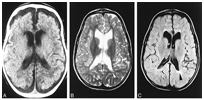

메틸말론산증이 있으면 신생아기부터 수유 후 구토와 식욕 저하를 보이며, 발달 지연과 성장 장애를 보입니다. 진단이 늦으면 의식이 없어지며, 탈수 현상이 심해지고 혈액이 산성화됩니다. 혈소판이 감소하여 출혈이 나타날 수 있으며, 백혈구가 감소하여 세균 감염에 노출됩니다. 치료하지 않으면 뇌 손상으로 인해 지능 저하, 경련이 나타날 수 있고, 사망에 이를 수도 있습니다. 신생아 시기에 진단되지 않은 채 정신 지체, 발달 지연 등이 나타나 영아기 이후에 진단되는 경우도 있습니다.